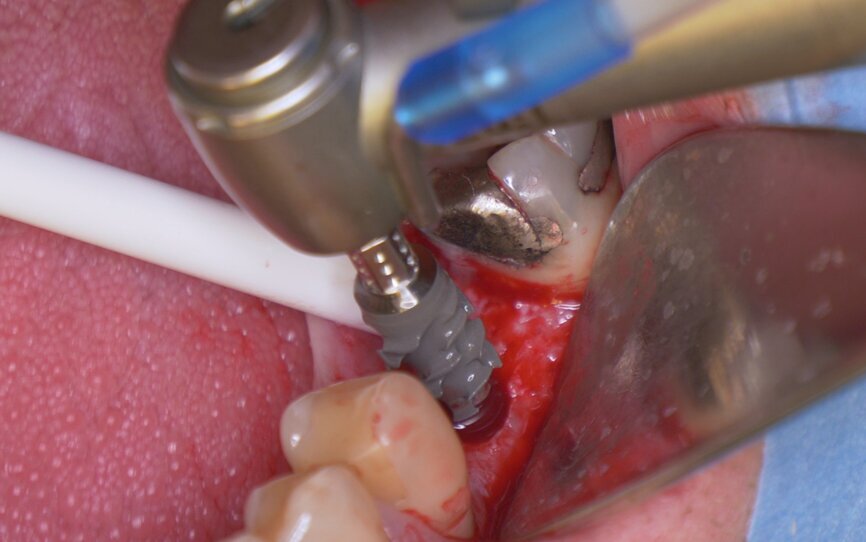

Fig. 4: Implant insertion with the handpiece at 15 rpm.

The patient, a 67-year-old non-smoking man without any relevant medical history, was referred to the office with a missing tooth (#36) due to persistent apical periodontitis. The tooth had been extracted more than one year prior to the procedure and the molar site was well maintained and fully healed (Fig. 1). A CBCT scan showed that the patient had favourable bone availability (Fig. 2), on which basis a one-stage placement of a 5.5 × 10.0 mm Straumann BLX implant was planned. After surgically installing the implant (Figs. 3–7), Salvesen allowed the surrounding soft tissue to mature and heal for six weeks (Fig. 8). He then removed the healing abutment to begin the prosthetic procedures for a temporary crown (Figs. 9 & 10). A stone master cast was made in the laboratory, and a temporary screw-retained PMMA crown was manufactured over a Straumann wide base temporary abutment for the crown (Fig. 11) and placed on to the implant (Figs. 12–14).

After 12 weeks, Salvesen removed the temporary crown, revealing that the soft tissue had healed very well (Fig. 15). He then began the digital workflow. For the final crown, a digital impression was taken with a 3Shape intra-oral scanner, using a Straumann CARES scan body. A monolithic zirconia crown was then seated passively on to the implant in a healed and preconditioned soft-tissue environment (Figs. 16–19).